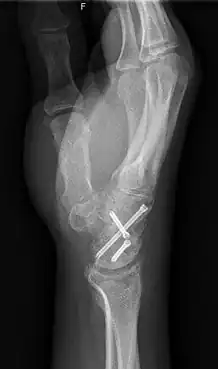

Arthrodesis is the surgical immobilization of bones within a joint to promote fusion of the joint.[5] Arthrodesis is performed most commonly on joints of the feet, hands, and spine.[6][7][8] Arthrodesis can relieve pain from arthritis and fractures.[9] This is accomplished through the use of orthobiologics such as allografts and autografts.[10] Allografts are done by creating bone grafts from a donor bone bank, whereas autografts are bone grafts from other bones in a patient's body.[10] Patient-reported outcomes following this procedure are typically positive in terms of long-term pain relief; however, the procedure also results in decreased range of motion.[11]

Implants

Alloprosthetic composites

Alloprosthetic composites are a combination of multiple limb-sparing techniques, namely allografts and prosthesis. Allografts are used to replace the bone that has been "resected" using arthroplasty techniques, and then prosthesis is used to support and strengthen the allografts.[16] Alloprosthetic composites are flexible in that surgeons can adapt the implants for any situation.[17]

Prosthetic implants

Prosthetic implants are used when sections of bone must be replaced and no further growth is expected. Implants are mostly made from metals, but the possibility of using ceramic material has been discussed among surgeons. Prosthetics can be temporary or permanent. Temporary implants remain in place until the bone has healed and are then removed. The temporary implants take most of the burden off of the fracture, causing the bone to become less dense. This can lead to re-fracturing of the bone after the implant is removed. The implants can also cause stress concentrations as a result of the material difference between the bone and the plate. With the permanent prostheses, a putty-like substance is injected into the implant site to keep the body, mainly the immune system, from fighting off the implant. This substance can deteriorate bony tissue and cause serious bone problems for the patient. Prosthetic limbs have been used for many years.